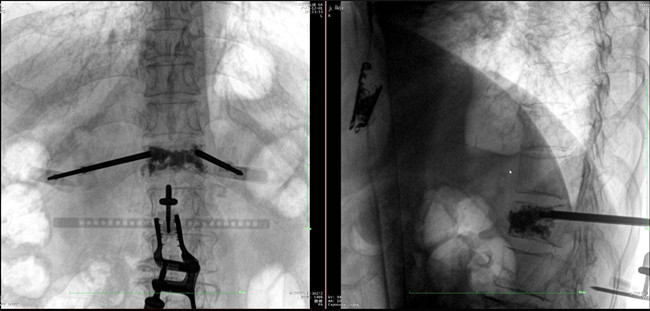

在病人體表切開一個長1-2cm的創(chuàng)口,沿骨科機器人的機械臂定位點方向將克氏針導向套筒,通過創(chuàng)口送至病灶椎體處,并沿套筒方向打入克氏針進行定位。沿導針插入工作套管,取出導針,完成球囊擴張后,通過骨水泥注入器準確地在骨折部位緩慢注入骨水泥,幫助其恢復椎體的形狀和強度。

? 手術效果確認

*骨水泥置入效果良好

良好的臨床使用體驗源于普愛醫(yī)療骨科機器人導航系統(tǒng)和醫(yī)生的完美配合。亞毫米級的準確定位、直觀的術前規(guī)劃和機械臂的執(zhí)行,使醫(yī)生無需擴大創(chuàng)口進行傷椎入針路徑定位,僅需術前三維重建即可全方位了解傷椎位置及穿刺路徑,除了極大的提高了一次性穿刺成功率,也大幅降低了手術對醫(yī)生經(jīng)驗的要求,手術上手難度更低。